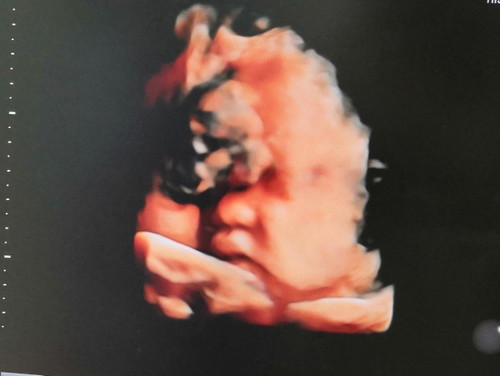

บ้านนี้กำหนดคลอด 14พ.ย. แต่ผลอัลตร้าซาวด์(ตอน38w.)น้องมีน้ำหนัก3,800 คุณหมอกลัวคลอดเองแล้วติดไหล่ เลยนัดผ่า 6 พ.ย.

เลือกคลอดธรรมชาติตั้งเเต่รู้ว่า ท้อง เเต่ตอนก่อนไกล้จะถึงกำหนดคลอด ประมาณ 1 สัปดาห์ ได้มีการตรวจครั้งใหญ่เพื่อประเมิณว่าจะคลอดอีกนานไหม หัวลูกลงมาหรือยัง หมอซาวด์ดูถึงขั้นตกใจ บอกเด็กขนาดรอบศีรษะกว้างมาก ตัวโต อยู่ในท่ากลับหัวเเล้ว เเต่หัวยังลอยอยู่ ประกอบกับ คุณหมอ ต้องไป ตปท. ก่อนกำหนดคลอดเรา ประมาณ 4-5 วัน ถ้าเราไม่ผ่าตอนหมออยู่ หมอจะส่งเคสต่อให้หมอคนอื่นทำคลอดให้ เลยตัดสินใจผ่าในวันถัดมาเลย เเละ เป็นการตัดสินใจที่ถูกมาก เพราะ ลูกน้ำหนักตัวเเรกคลอด 3,860 กรัม ยาว 55 ซม. ตัวใหญ่ เเละ ยาวสุด ในห้อง เนิร์สเซอรี่ ถ้าเกิดวันนั้นเลือกที่จะคลอดเอง คงเจ็บ 2 ต่อ ไม่ก็เเผลฝีเย็บคงใหญ่มากๆ ตัวใหญ่ขนาดนั้น หรือ ไม่ก็อาจจะเบ่งไม่ออก ใช้เครื่องช่วยดูด หรือ อาจจะต้องผ่า เพราะ คุณเเม่เป็นสาวร่างบาง กระดูกเล็ก เลือกวิธีที่ เซฟ ลูกเรา เเละ ตัวเรา มากที่สุดค่ะ จะคลอดเเบบไหนไม่สำคัญหรอก สำคัญที่ ทุกคนปลอดภัย มากกว่า เรื่องเจ็บไม่เจ็บนี่เป็นเรื่องรองลงไปเลย

ลูกชายผ่าคลอดเพราะตัวใหญ่ไม่กลับหัวคะ เพื่อความปลอดภัยแม่และลูก คลอดออกมา 4.05คะ ท้องแรก

หมอบอกลูกตัวโต กลัวว่าจะคลอดเองไม่ไหว เลยแนะนำให้ผ่า

ตอนนั้น 39week น้องน้ำหนัก 3,800 กว่านี่แหละ ค่ะ คุณหมอเลยแนะให้ผ่าค่ะ ของคุณแม่น่าจะหนักว่าเพราะยัง38week